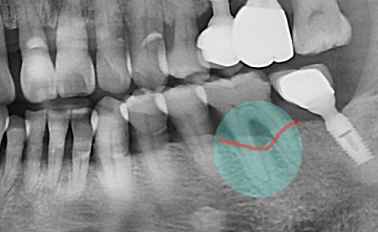

네비게이션 임플란트

네비게이션 임플란트가 필요한 경우